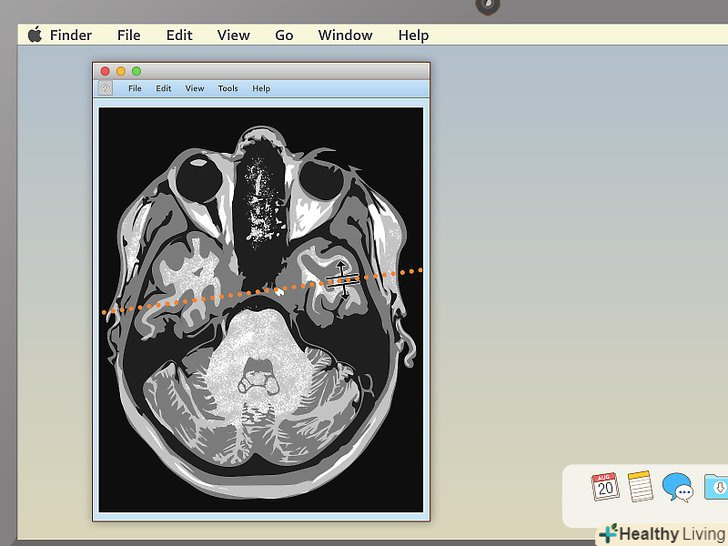

Натисніть на спеціальну лінію, щоб побачити, де перетинаються проекції.якщо ви вирішите відкрити зображення з пересічними проекціями, ви побачите особливу пряму лінію, що перетинає зображення. Вона буває не на всіх записах. Якщо на вашій її немає, на другому знімку буде показано, де знаходиться область перетину. [7] ви зможете зміщувати лінію до центру, направо і наліво. Це дозволить розглянути органи під іншим кутом.- Лінія також вкаже, з якого боку був зроблений знімок. Наприклад, якби МРТ був знімком звичайного предмета (наприклад, дерева), лінія вказала б вам на те, звідки була спрямована камера: зверху з літака, з вікна другого поверху або з землі.

Перетягніть лінію, щоб розглянути різні області на знімку.це дозволить вам переміщатися всередині зображення. Знімок буде автоматично змінювати проекцію.- Наприклад, якщо ви розглядаєте зображення хребта в саггитальной площині і також завантажили область з пересічними площинами, рухаючи лінію, ви зможете вивчити хребці як зверху, так і знизу. Цей інструмент особливо корисний для діагностування грижі міжхребцевих дисків.